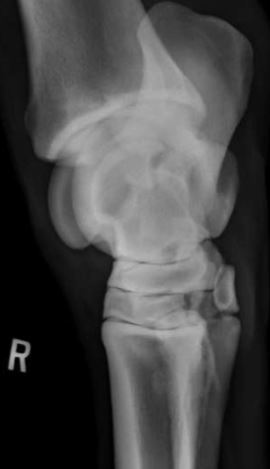

What view is this?

A

DLPMO

Q

DMPLO

On which view can you see both ridges of the talus?

Which aspects are viewed in a DLPMO

Dorso-medial

Lateral-plantar/palmar